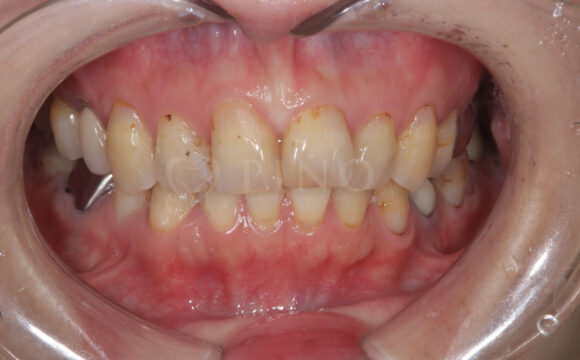

症例2:ワイヤー矯正後の後戻りが気になる(50代女性)

主訴 ワイヤー矯正後に後戻りが気になる 診断名 叢生 治療方法 マウスピース部分矯正 抜歯 なし オルソパルス なし 治療期間 10ヶ月 費用 436,000円+補綴費用360,000円 副作用・注意点 矯正後の後戻りを防ぐためリテーナーの使用が必要となる 備考 1年4ヶ月で補綴も完了した -